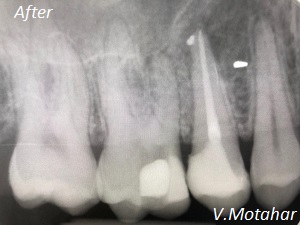

Root canal treatment on three rooted tooth! which had 4 canals!